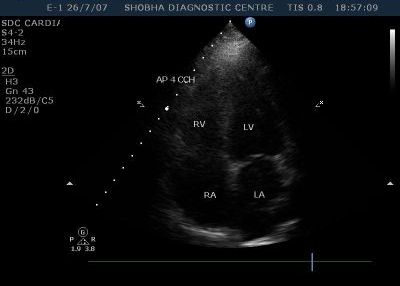

2D & Color Doppler Echo

2D Echo with Doppler is an examination that is performed on the ultrasound machine to detect abnormalities of the heart. It is used in many situations to detect cardiac function and ejection, valve motion, as a pre operative fitness test, to look for fluid around the heart, and motion abnormalities.